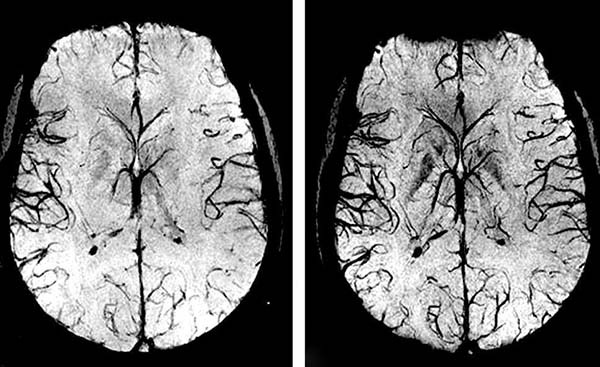

- Enfermedades cerebrovasculares. Se caracterizan por una violación de los vasos del cerebro, lo que conduce a una falta de nutrición de las células cerebrales y, como resultado, daño a su sustancia. A menudo conducen a un derrame cerebral, que causa la muerte o discapacidad de una persona.

- Buenas tardes. En su mayor parte, los síntomas de varias enfermedades cardiovasculares son muy similares. Es por eso que no siempre es posible hacer un diagnóstico correcto: podemos sospechar hipertensión crónica, pero de hecho resulta que el paciente tiene angioedema cerebral. Esta patología a menudo imita otras anomalías.

Aunque las anomalías vasculares no siempre causan enfermedades agudas, son muy insidiosas. Los problemas en el sistema cardiovascular en un gran número de casos conducen a accidentes cerebrovasculares, diversas enfermedades crónicas, trombosis, síndrome coronario agudo y otras enfermedades peligrosas.

Si los vasos sanguíneos del corazón (arterias coronarias) están obstruidos con depósitos de

colesterol, esto inicialmente causa angina, pero luego puede provocar un infarto de

miocardio. Y los vasos perdidos que no entregan la cantidad correcta de sangre al cerebro

son el camino directo para un derrame cerebral.